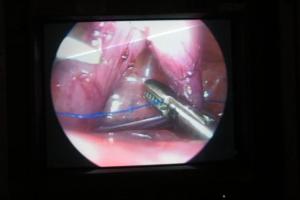

Santa Casa realiza com sucesso primeira videotoracoscopia do Norte do Brasil